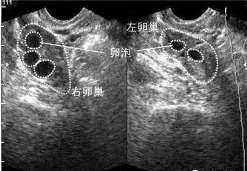

B超检查